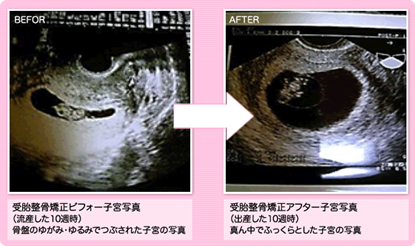

左はトコちゃんベルト着用前(7㎝の骨盤のゆるみ)⇒右は着用後(2㎝の骨盤のゆるみ) 流産歴が数度あり、今回の妊娠後も出血など不安定で来院。

左の写真で骨盤のゆるみが7㎝以上あり、子宮内の胎嚢の形状が悪いので、トコちゃんベルトを正しく着用を指導しました。 着用後は右の写真、丸くふっくらとした子宮内の胎嚢の写真になりました。(2㎝の骨盤のゆるみ) その後無事に出産されました。喜びの手紙を頂きました。